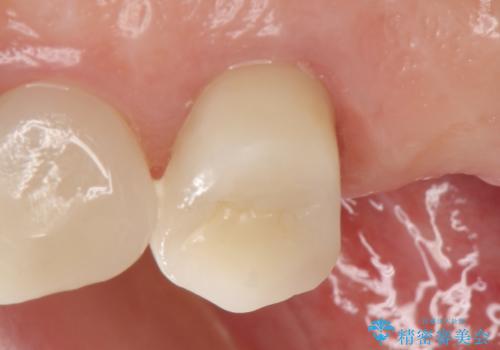

今回用いたオールセラミッククラウンはジルコニアフレームという白い素材の上にセラミックを盛っているため、審美性が非常に高いのが特徴です。

また、ジルコニアは人工ダイヤモンドの材料にも使われているほど高い強度を持っており、そのためオールセラミッククラウンは審美性だけでなく、奥歯やブリッジの補綴も可能とするクラウンです。